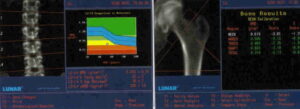

Il reumatologo di oggi può contare su farmaci innovativi, come i biologici, ma ha anche a sua disposizione strumenti diagnostici...